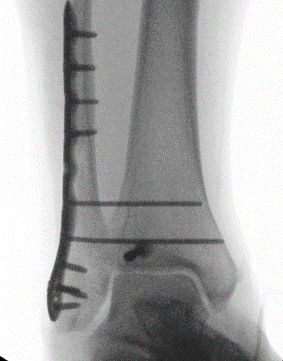

Fixation

Buttress plate

PA screws

Posterolateral buttress plate